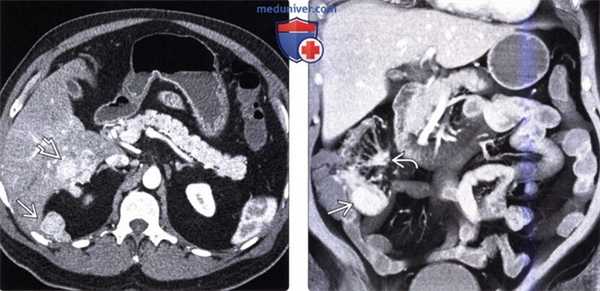

(Слева) На аксиальной КТ с контрастным усилением у мужчины 65 лет с жалобами на боль в животе визуализируется объемное образование в брыжейке с наличием кальцинатов в центре, видны также переполненные кровью брыжеечные сосуды. В правом нижнем квадранте также определяется стягивание брыжейки с деформацией кишечника.

(Справа) На КТ, полученной в венозную фазу контрастного усиления, визуализируется подозрительное объемное образование в илеоцекальной области, которое, как подтвердилось при хирургическом вмешательстве, является карциноидной опухолью. Обычно метастазы в брыжейке более очевидны на КТ по сравнению с первичной опухолью, особенно в венозную фазу контрастного усиления.

3. КТ при карциноиде (карциноидной опухоли):

• Подслизистые опухоли:

о Солитарные или множественные, четко отграниченные, накапливающие контраст:

- 80-95% карциноидных опухолей-гиперваскулярные

о Объемное образование в стенке, усиливающееся при контрастировании, лучше визуализируется при дополнительном приеме воды в качестве контрастного вещества

о Первичную опухоль выявить сложнее, чем вторичные очаги

• Распространение опухоли тонкой кишки в брыжейку:

о Объемное образование в брыжейке неоднородной структуры, возникающее вследствие прямой инвазии или метастатического поражения лимфоузлов

о Вплоть до 70% случаев в образовании брыжейки обнаруживаются кальцинаты

о Возможна также деформация, фиксация, ретракция петель тонкой кишки:

- Обусловленная фиброзом брыжейки и десмопластической реакцией

- Десмопластическая реакция проявляется пальцевидными выпячиваниями от образования в прилежащую брыжейку

о Возможно также обрастание и сужение брыжеечных сосудов

о Обструкция тонкой кишки может быть обусловлена новообразованием в ее просвете, перегибом или инвагинацией

(Слева) На аксиальной КТ у мужчины 54 лет со схваткообразной болью в животе и приливами визуализируются гиперваскулярные метастазы в печени и по брюшине.

(Справа) На корональной КТ у этого же пациента визуализируется гиперваскулярное образование в терминальных отделах подвздошной кишки (первичная опухоль) в сочетании с метастазами в брыжейку с наличием десмопластических изменений в брыжейке подвздошной кишки. Эти клинические и лучевые признаки являются классическими изменениями при карциноидном синдроме.